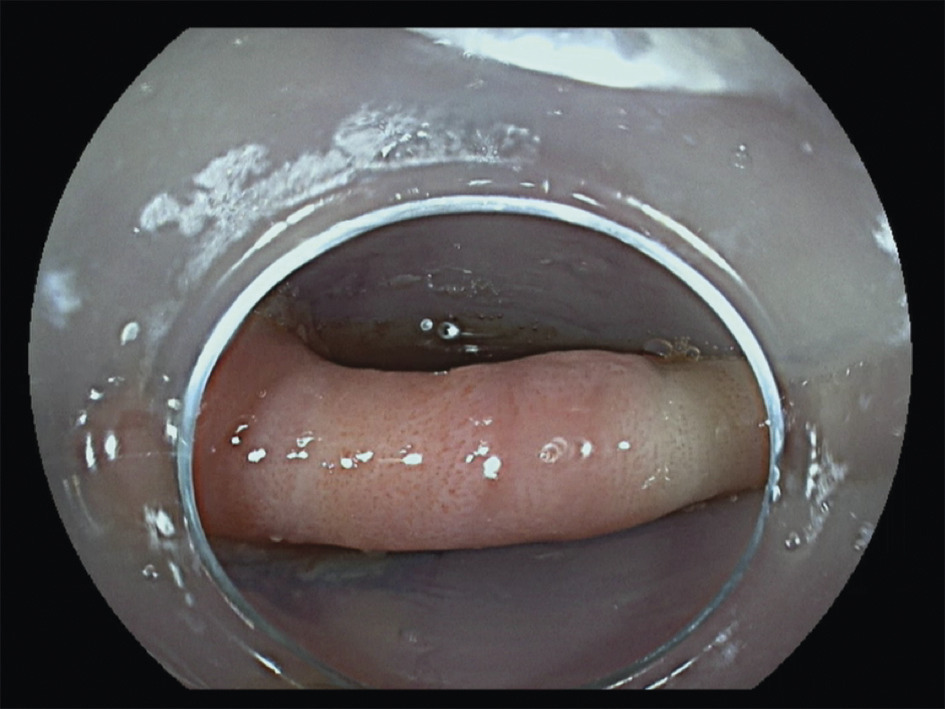

Le traitement endoscopique (fig. 2 à 5 ), ou myotomie transmuqueuse du cricopharyngien, peut être pratiqué par les ORL avec un diverticuloscope rigide ou par les gastro-entérologues experts, par endoscopie souple.2 Le diverticuloscope rigide impose une hyperextension cervicale parfois limitante. La diverticulotomie endoscopique consiste en une section de la paroi séparant le diverticule et l’œsophage, comprenant le muscle cricopharyngien, jusqu’à 5 mm du fond du diverticule. Elle offre des avantages par rapport à la chirurgie classique en termes de durée de procédure (< 1 heure) et d’hospitalisation. La réalimentation est plus précoce.

Le traitement endoscopique consiste en une section du septum diverticulaire séparant le diverticule de la lumière œsophagienne, jusqu’au fond du diverticule, après création d’un tunnel sous-muqueux.3 Dans le même temps, en prolongeant le tunnel en aval, une myotomie peut être réalisée jusqu’au cardia, traitant ainsi le trouble moteur associé.